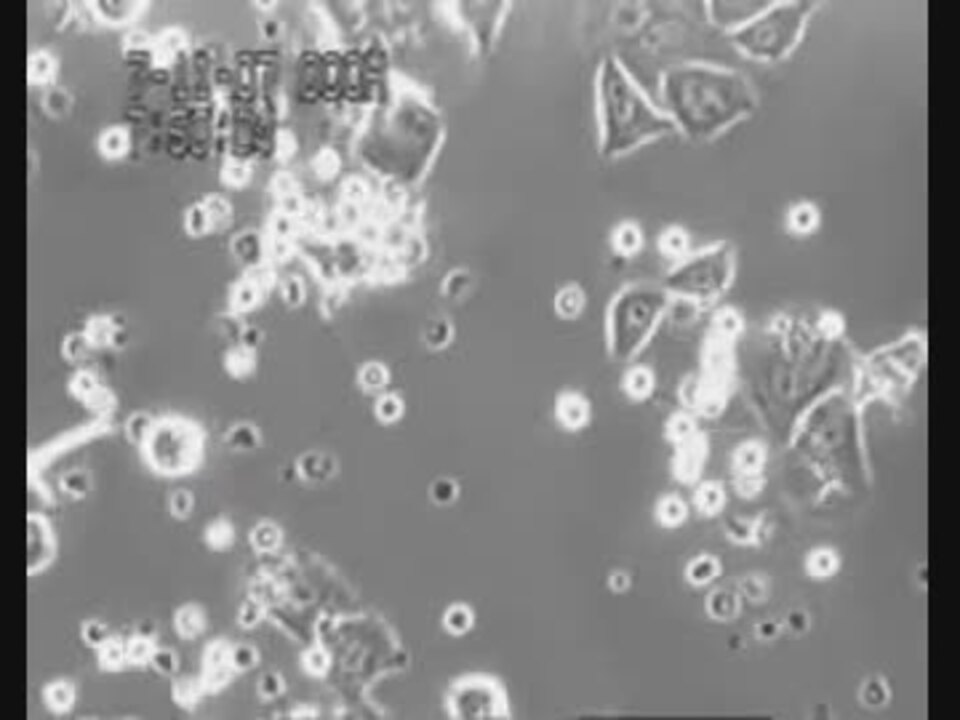

ガン細胞を白血球が攻撃する映像 0:38